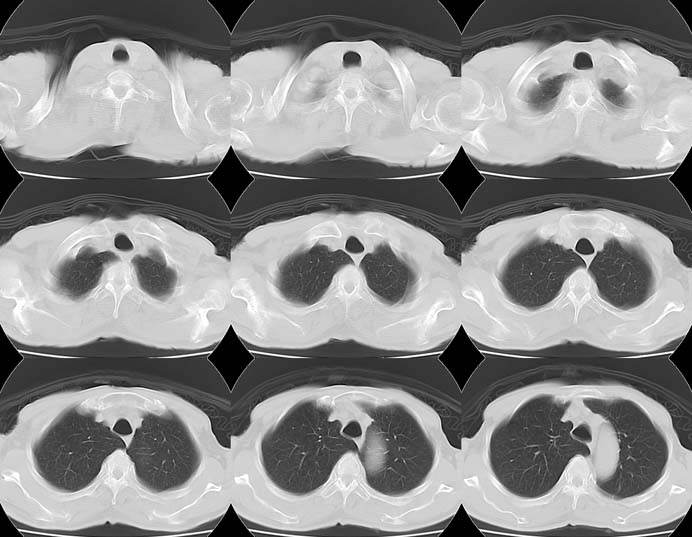

Lung Cancer: Adenocarcinoma:"High-speed screening mode."

8mmx4, Pitch 6, 384mm, 4-seconds, 150-mAs: